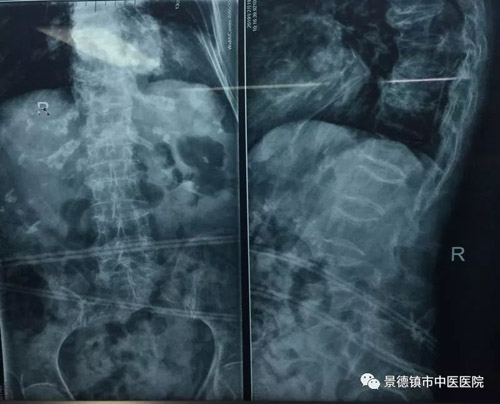

上圖為麻醉科主任們嚴密觀察患者病情及實施手術前的麻醉